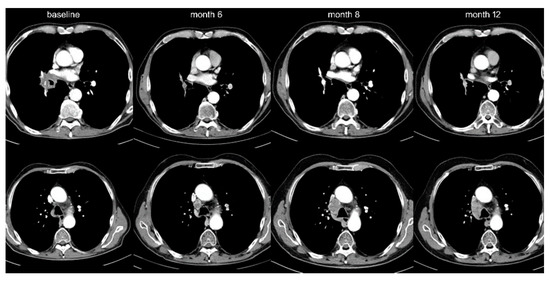

Among IO-monotherapy patients, 38 (13%) showed OPD with decreasing frequency beyond the first line (20% vs. 10%, p < 0.05, Table 1, Figure 1). Furthermore, OPD in patients treated with IO monotherapy in the first line occurred later (after 11 vs. 2 months in median, p < 0.001), involved fewer anatomical sites (mean 1.1 vs. 1.5, p < 0.05), and affected fewer lesions (mean 1.4 vs. 2.3, p < 0.05) compared to OPD in patients receiving IO monotherapy in later lines (Table 2). Lymph nodes (42% of OPD cases, mainly mediastinal, Figure 2 and Table 2) and brain (39%) were affected most frequently, but OPD was also observed in other organs typically affected by NSCLC, namely lung (24%, Figure 3), adrenal glands (16%), bone (8%), liver (5%), skin and soft tissues (3%).

Figure 3. Lung oligoprogression and transitional cell carcinoma of the kidney. A 75-year-old female with adeno-NSCLC (PD-L1 90%) was started on pembrolizumab in September 2017 with response of the primary tumor, mediastinal lymph nodes, and liver metastases. Upon oligoprogression of the primary tumor in March 2018, thoracic radiotherapy was administered. In August 2018, a new kidney lesion was noted that grew oligoprogressive-like. At biopsy, this lesion turned out to be a transitional-cell carcinoma.

The main study population encompassed all 372 stage IV NSCLC patients with radiologically documented disease progression under PD-1/PD-L1 inhibitors among all 636 IO-treated patients in our hospital from March 2013 until September 2019. Treatment consisted of either checkpoint inhibitor monotherapy in various treatment lines (454 IO-monotherapy patients, of which 297 had radiologic evidence of disease progression at the time of study inclusion) or upfront combined chemoimmunotherapy (106 patients, 75 of which with radiologic progression, Figure 1). For analysis, the study population was divided in three groups: patients with IO monotherapy in the first line (n = 89), who were contrasted to patients with IO monotherapy in subsequent treatment lines (n = 208) and to patients with chemoimmunotherapy in the first line (n = 75, Table 1). Imaging studies were performed according to the standard in our institution with chest/abdomen CT and brain MRI scans before treatment start and every 6–12 weeks thereafter (Figure 2). Cases with disease progression suitable for inclusion in this study were identified by a retrospective review of medical records, followed by a review of radiological images in order to characterize the progression pattern as diffuse or OPD. Other clinical parameters were collected from the patients’ records (Table 1). Patients with early death before the first restaging, and patients who died during the stable phase of the disease after the initial response due to other reasons, were non-evaluable and excluded from this analysis (n = 66). Patients with chemoimmunotherapy after pretreatment with tyrosine kinase inhibitors for actionable genetic alterations were also excluded from this study because of potential biologic differences (n = 10, Figure 1). Testing for actionable EGFR/ALK/ROS1/BRAF mutations had been performed as indicated (e.g., in case of adenocarcinomatous histology or never/light-smoker status) for all patients at initial diagnosis, followed by administration of targeted therapies if positive, so that practically no cases with treatable genetic alterations were included in this analysis.